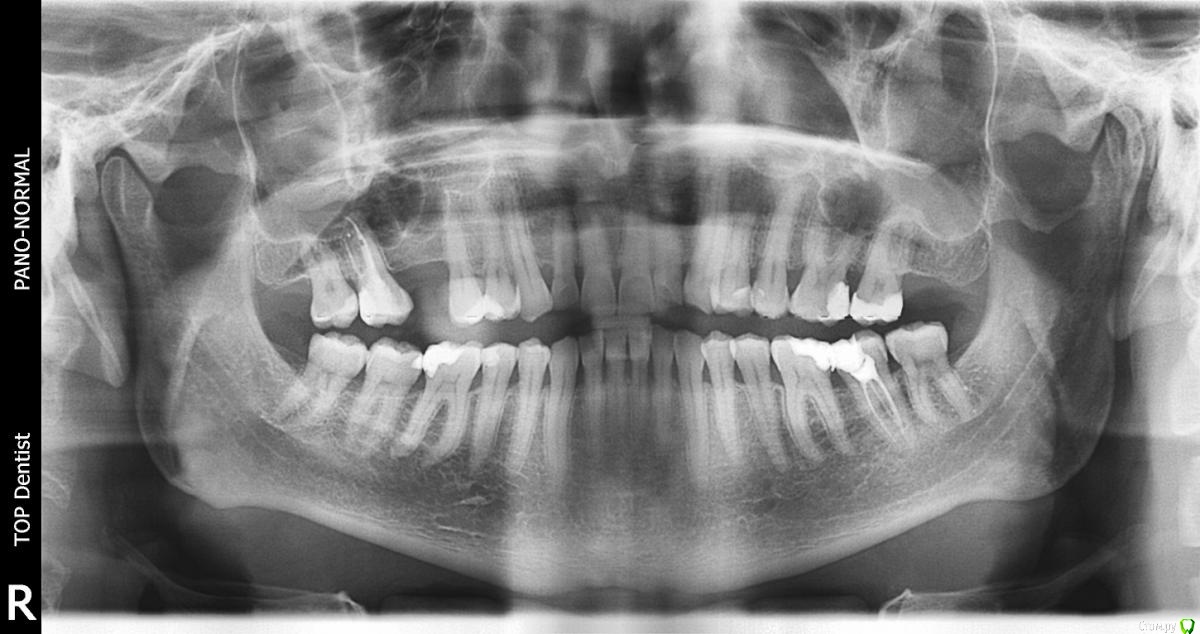

al7777 Опубликовано 10 января, 2021 Автор Поделиться Опубликовано 10 января, 2021 Доехал до Пикассо, сделал новый панорамный снимок.Так лучше? 1 Ссылка на комментарий